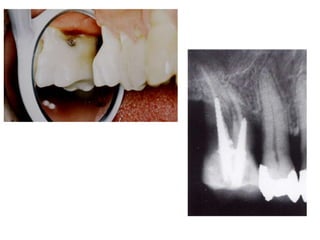

TRATAMENTO DAS LESÕES

ENDOPERIODONTAIS

Hemisseccção

DEL RIO, 1996